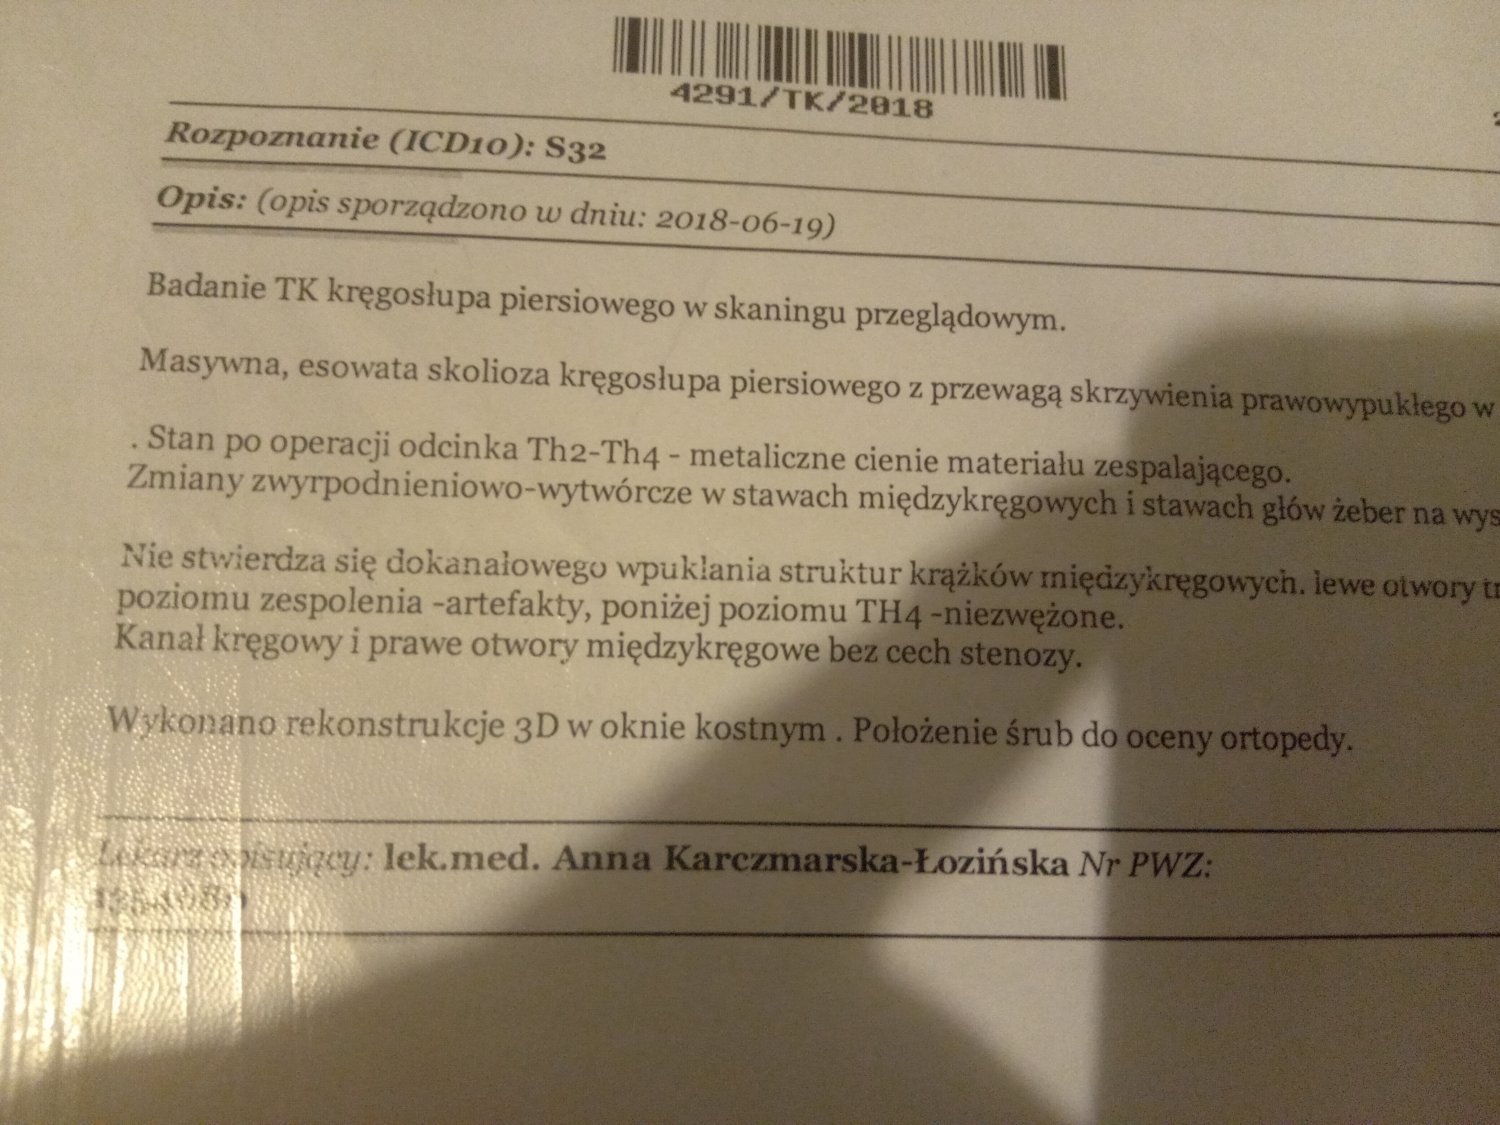

Witam jestem samotną matką wychowująca dwójkę dzieci . Spodziewam się córeczki jestem w 18 tygodniu ciąży moje problemy zaczęły się gdy miałam 18 lat i miałam wypadek samochodowy . Straciłam władzę w kręgosłupie ponieważ mam implanty w kręgosłupie piersiowym oraz przepuklinę krzyżowa. Dlatego też nie jestem wstanie pracować bo każdy wysiłek fizyczny to bardzo duży ból